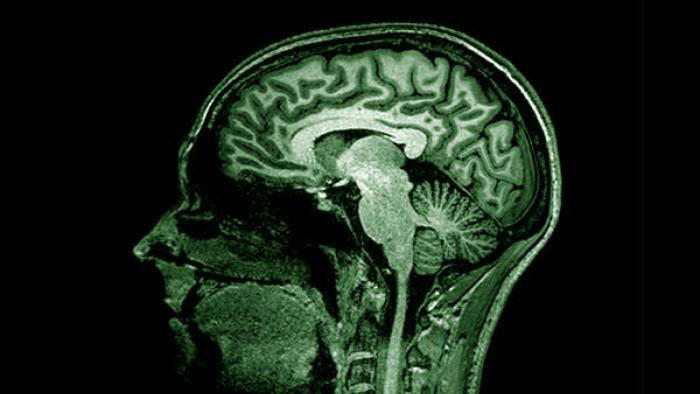

The Neuroimaging Research Group focuses on the study of magnetic resonance imaging (MRI) and positron emission tomography (PET) images to reveal pathophysiological changes associated with Alzheimer’s disease and healthy aging that can be informative of novel prevention strategies. With this purpose in mind, neuroimaging data are analyzed together with cognition, genetics, biomarker and other clinical, environmental and lifestyle factors to detect their impact on the brain at the structural, functional, and molecular levels. The Neuroimaging Research Group is composed of a multi-disciplinary team of experts on data acquisition, processing, and analysis of complex neuroimaging data.

Neuroimaging techniques, like MRI and PET, allow us to characterize brain alterations in the preclinical stage of Alzheimer’s disease to better understand the physiological processes involved in the response to the onset of early cerebral pathological changes.

This line focuses on developing novel and more convenient methods to improve the detection of pathophysiological alterations in Alzheimer’s disease. To this end, the group develops novel MRI pulse sequences that are sensitive to changes associated with the accumulation of misfolded proteins in the brain.